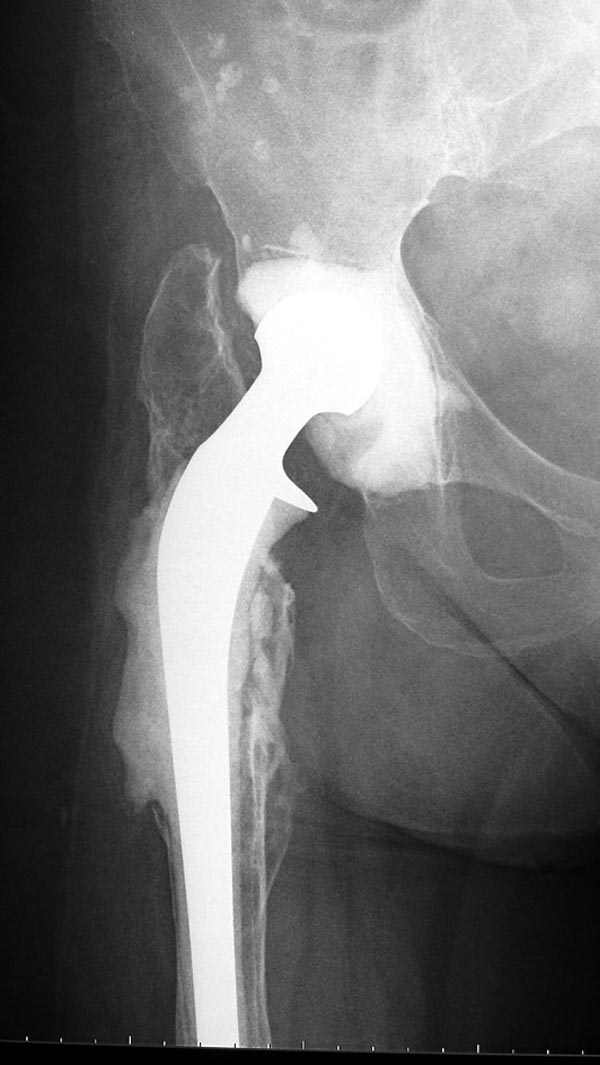

Если снимок справа по хронологии последний, то в тазобедренном сустава наступил анкилоз. Это хороший плюс костной ткани для постановки чашки эндопротеза, но отсутствие сохранения биомеханической оси бедренной кости ставит под вопрос благоприятный вариант усановки ножки эндопротеза.... Учитывая выполненную остеотомию, не считаю выполнение скелетного вытяжения лишенным смысла, для восстановления оси конечности с последующим, возможно, индивидуальным эндопротезированием.

Очень признателен Вам за ответ, но позвольте мне не согласиться с Вами. Я бы пока не делал вывод о анкилозировании тазобедренного сустава. На рентгеновских снимках, да и по данным компьютерной томографии (а этот метод один из самых современных и информативных), хорошо прослеживается постоянной ширины щель между головкой бедренной кости и вертлужной впадины. Кроме того, несложно увидеть разницу "шеечно-диафизарного угла" до и после выполнения тракции в аппарате. Хотя, Алексей, даже если я и прав, это не сильно облегчает нашу задачу.

Вот снимки по свежей ситуации, парень 19 лет, длинный оскольчатый перелом бедра от шейки до в-с/3. давно уже ходит на своих ногах.

Представленные Вами рентгенограммы действительно являются примером качественной фиксации спице-стержневым аппаратом. Они, как ни что другое, многое иллюстрируют.

Кроме того, было бы ошибкой ставить знак равенства между нашим и Вашим пациентами. Они не только не похожи, разница между ними просто огромная. Говорю это не для того, чтобы задеть Вас или обидеть. Ни в коем случае. Просто теперь я понимаю, что Ваше мнением строится на простом преломлении Ваших подходов к лечению пациентов со свежими переломами, на ситуацию, абсолютно несопоставимую, подобную нашей.